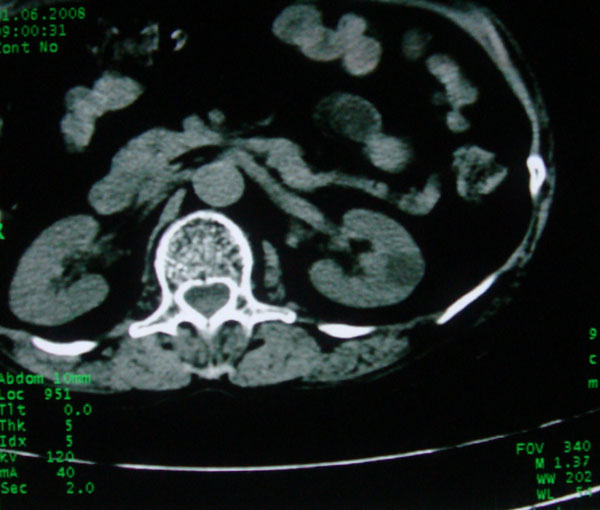

患者女性体查.发现左肾有低密度影,大家考虑是什么.其它方面没有什么异常.低密度影ct值约22hu.

左肾低密度影,境界尚清,查体发现,临床无其他首先考虑肾囊肿,如果增强一下对鉴别有帮助。

左肾不均匀低密度,其形态不规则、边界不清楚,更谈不上锐利。虽无局部凸出,但最后一张片显示仍有比较明显的隆起,我多考虑为肾癌,建议增强或mri检查。

左肾肾实质内低密度灶,性质待定。建议:行进一步检查。